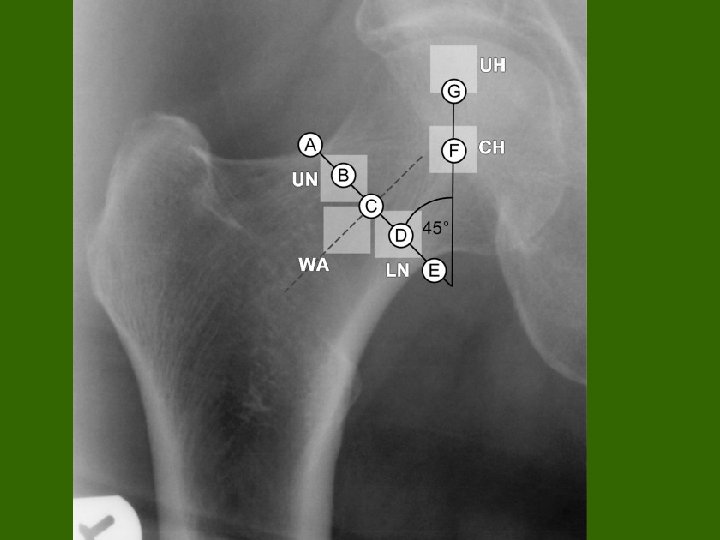

Vrat femura (collum femoris) – česte frakture, naročito kod osteoporotičnih kostiju (menopauza, poremećaj metabolizma kalcijuma kod nekih endokrinih bolesti i sl. ) - Definisali smo geometrijski(matemtički) model vrata femura – klinički značajno zbog adekvatne pozicije šrafova kojima se pričvrščžćuju delovi vrata kod fraktura vrata - trohanteri (veliki i mali) – definisati tzv. “trohanterični region“ gornjeg okrajka (proksimalnog femura) - značaj tzv. kolodijafiznog ugla - značaj tzv. subcapitalnih fraktura - rentgen anatomija proksimalnog okrajka femura

- istraživanja sprovedena na: - tzv. “suvim modelima kostiju“ – kosti iz anatomskih zbirki -na rentgem snimcima -na CT i MRI snimcima -na ultrazvučnim snimcima -definisani karakteristični geometrijski parametri proksimalnog okrajka značajni za izradu njegovog matematikog modela